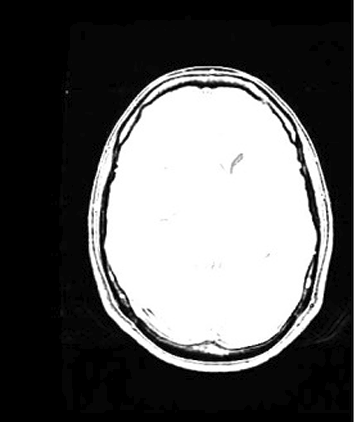

Table 6 Fused image output.

From: Multimodal medical image fusion combining saliency perception and generative adversarial network